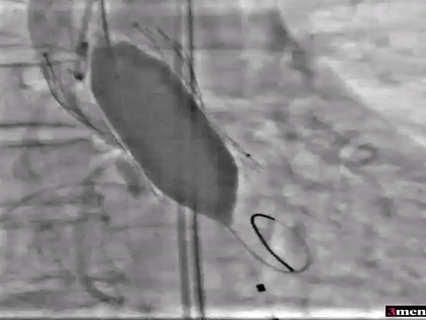

患者二手术情况

在放射科,超声科和麻醉科的通力协作下,顺利完成了术前准备,术者团队在术中谨慎建立轨道,根据主动脉根部造影的结果选择合适的跨瓣体位。

瓣膜释放后造影